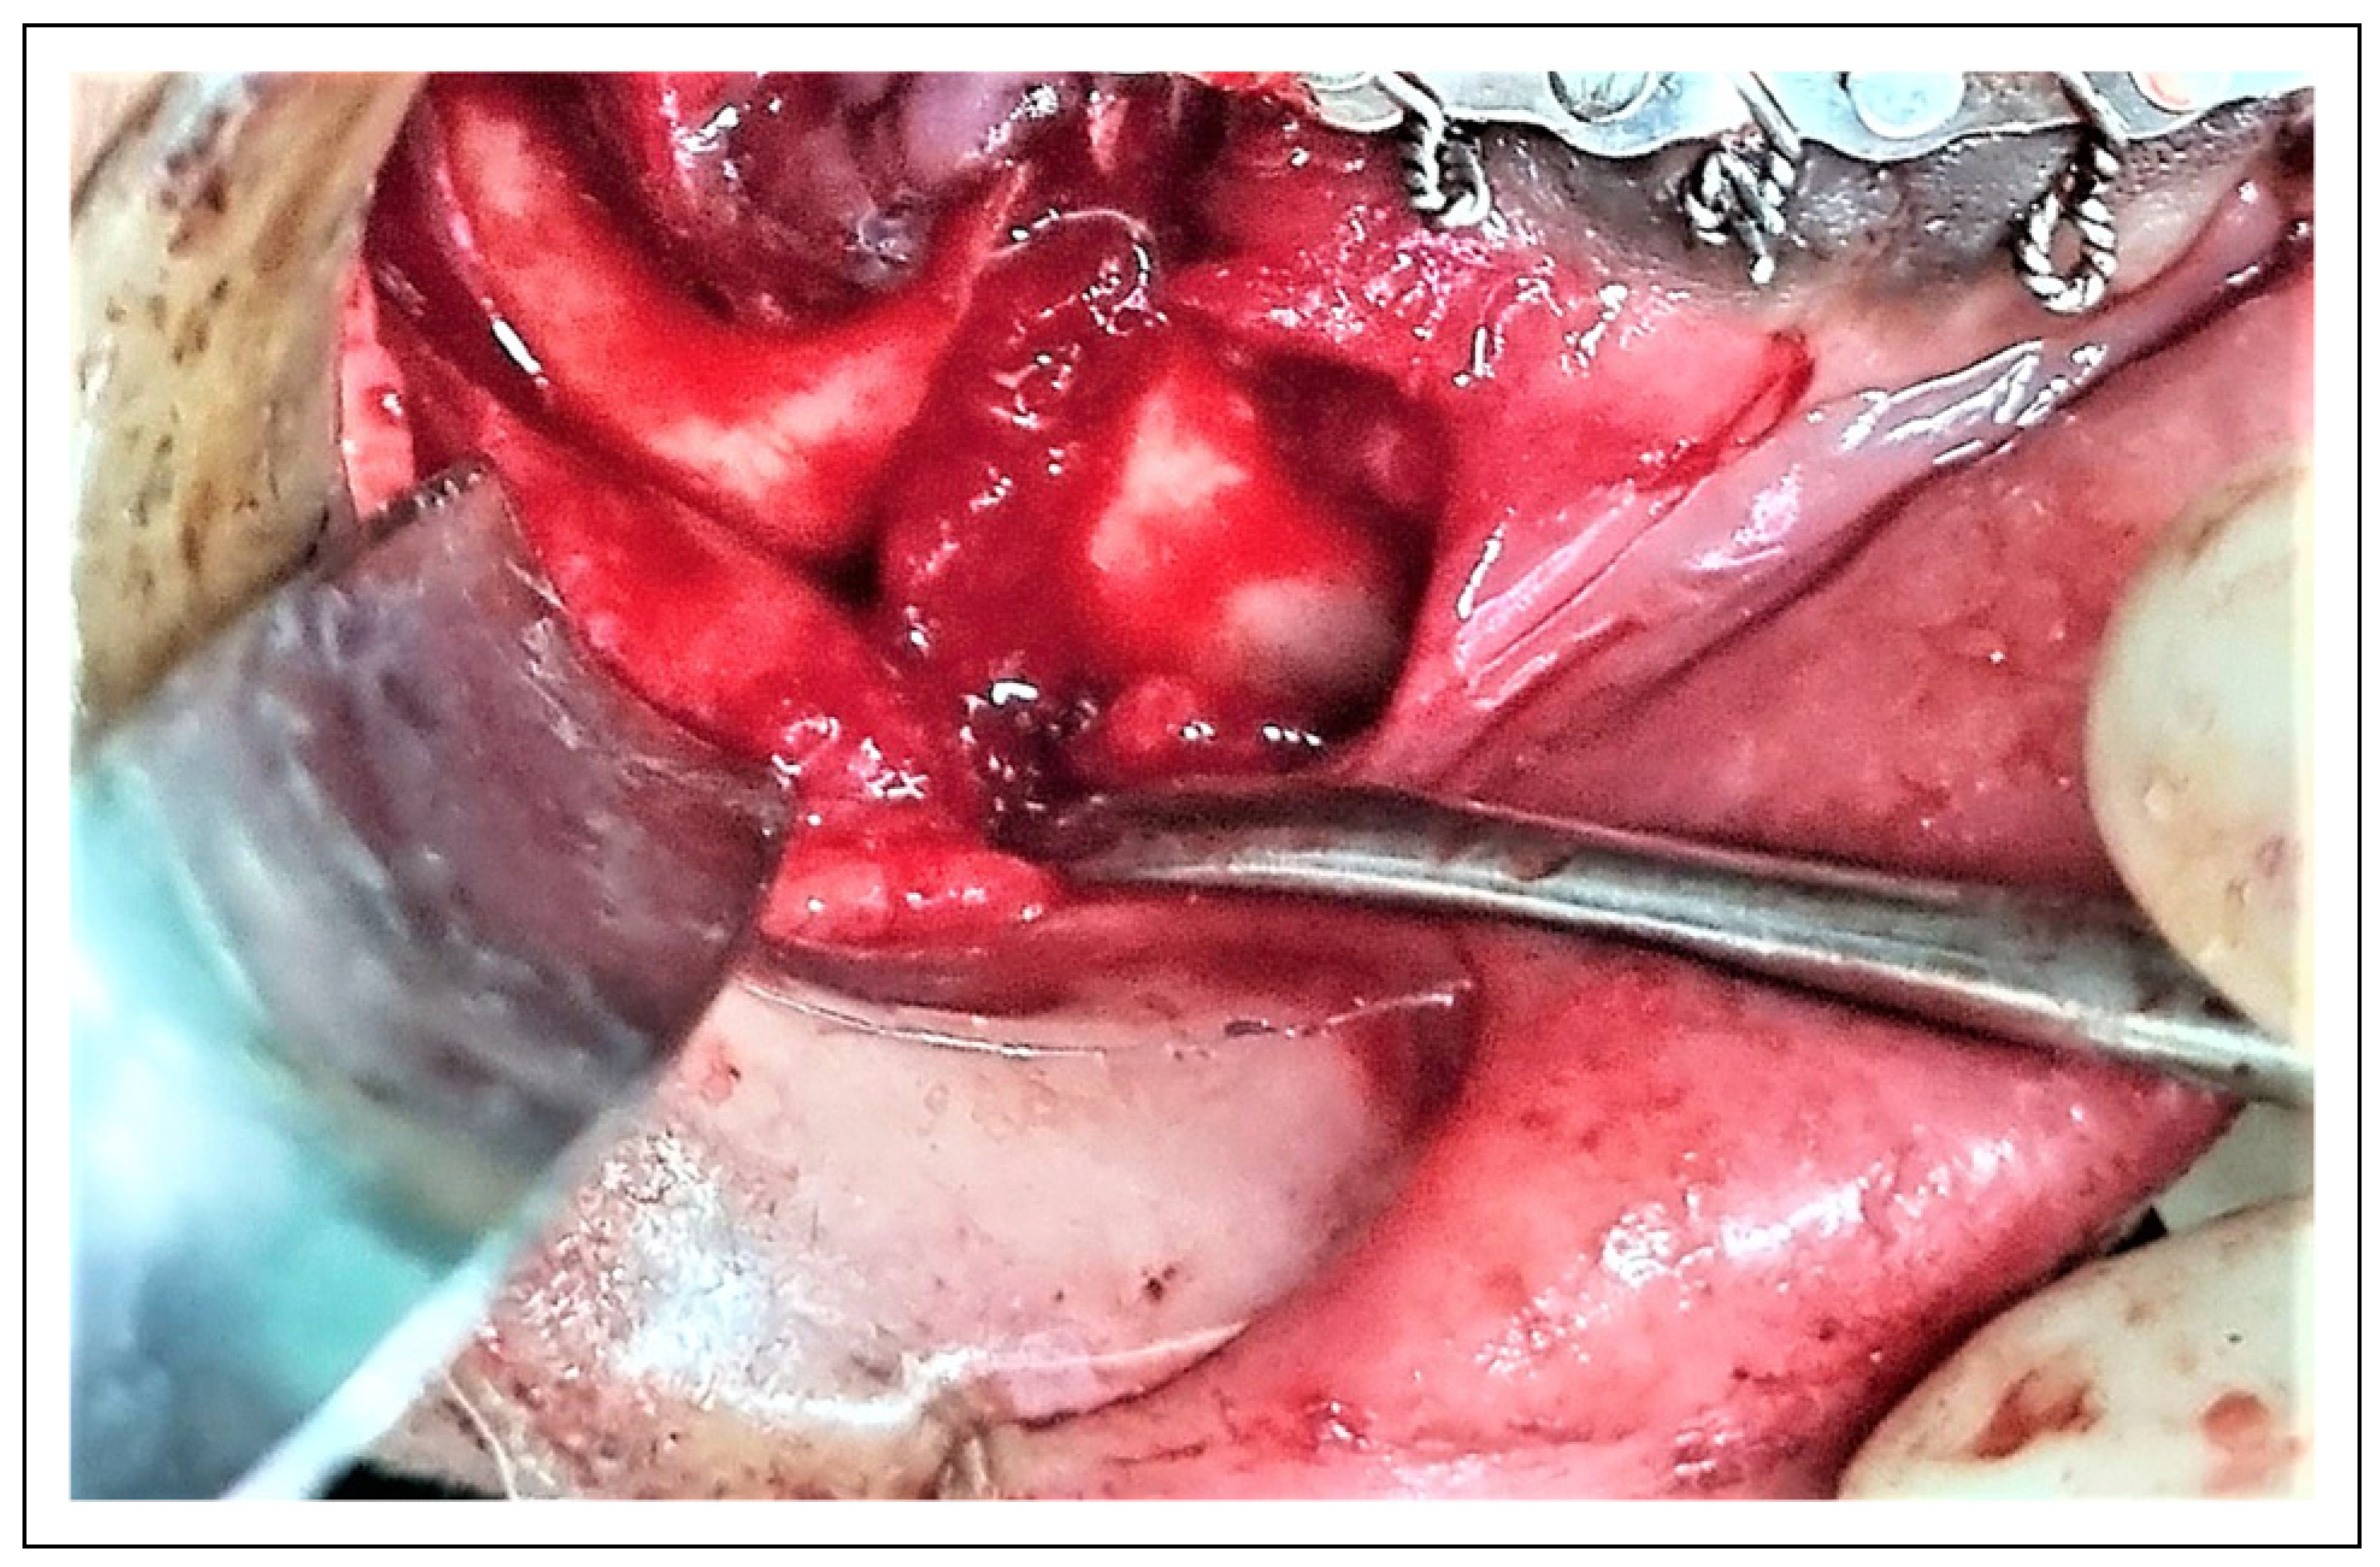

Surgical Procedure